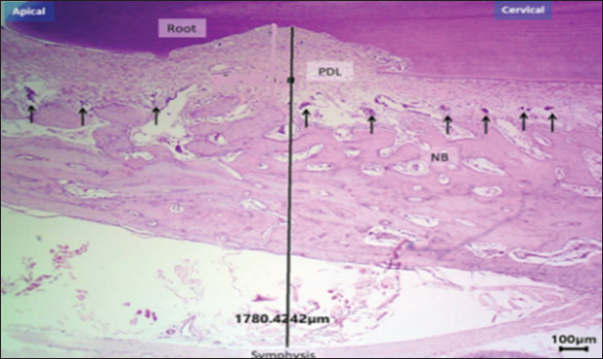

Based on the histomorphometric findings, exogen treatment markedly enhanced bone-forming activity, as evidenced by a statistically significant increase in osteoblast count at both day 10 and 20 compared with the control group (p < 0.01), indicating accelerated bone formation. In contrast, osteoclast count was significantly reduced at day 20 (p < 0.05), reflecting suppression of bone resorption. Vascular density showed a consistent and significant increase across all post-removal time points (p < 0.01), providing a more favorable blood supply for bone and periodontal tissue healing. Additionally, PDL width was narrower in the Exogen group by day 20, suggesting enhanced tooth stability after orthodontic appliance removal. Representative histological sections at day 10 are shown in Figures 7 and 8.

This pattern of results translates into accelerated healing of bone and periodontal tissues with an improved vascular environment, supporting the hypothesis that LIPUS can reduce post-treatment tooth relapse and promote long-term stability (Fig. 9a and b). New bone surface distribution is demonstrated in Figure 10.

Fig. 9. Histological section of the control group at day 20 showing disorganized new bone (NB), widened PDL space, and multiple osteoclasts (arrows). H&E stain, 40×, scale bar=100 μm.

Fig. 10. H&E –stained sections representing new bone surface area in control and exogen groups along cervical and apical lines at day 0. H&E, 100×, scale bar=100 μm.